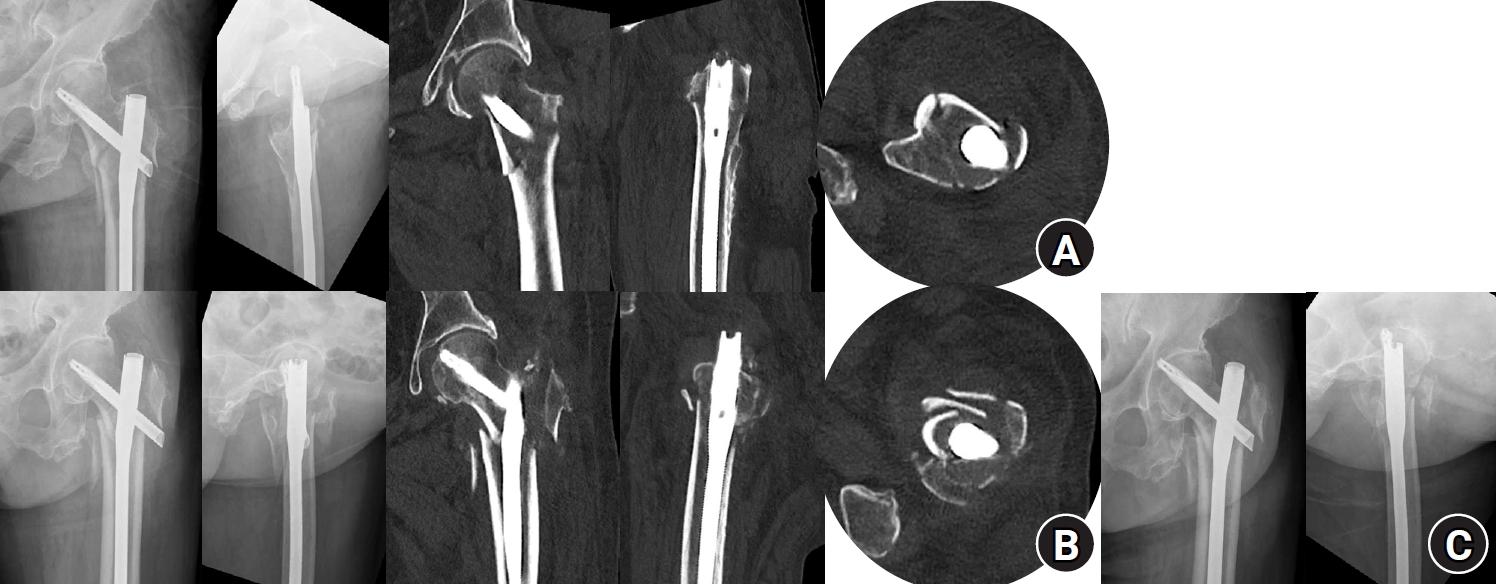

Fig. 6.

Radiographic images of an 82-year-old female patient with an AO/OTA intertrochanteric femur fracture classification of A3 treated with the percutaneous anterior leverage technique. (A) Postoperative radiographs showing positive medial cortical support and neutral anterior cortical support; (B) Radiographs taken 3 weeks postoperatively (at the first outpatient visit) showing conversion to negative anteromedial cortical support with cortical breakage; (C) Radiographs taken 7 weeks postoperatively showing blade cut-through.

jmt-2025-00311f6.jpg

Bone union was achieved in 50 patients (94.34%), with a mean time to union of 3.93±1.48 months. The mean change in the neck-shaft angle between the postoperative period and the final follow-up was 1.75°±2.34° in varus. Nonunion in the absence of varus collapse or blade cut-through occurred in one patient (1.89%), and blade cut-through in one patient (1.89%). Varus collapse was seen in one patient (1.89%), despite the achievement of bone union during long-term follow-up. This case was classified as a treatment failure. Thus, three cases (5.66%) in total were categorized as treatment failures (Table 3). Interestingly, all instances of anteromedial cortical breakage during follow-up were in patients who experienced treatment failure (Fig. 6). Specifically, it occurred in the patients with blade cut-through and varus collapse. It was not seen in the patient with nonunion in the absence of varus collapse or blade cut-through, in whom reduction was maintained, but bone union was not achieved. This patient had multiple comorbidities—including bladder cancer, chronic kidney disease, cerebral infarction, alcoholic liver cirrhosis, diabetes, and hypertension—and it is presumed that these host factors contributed to the development of nonunion.